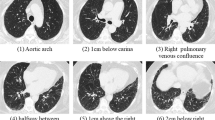

Quantitative CT analysis is one area of the rapidly developing field of radiomics. Radiomics can extract, analyze, and interpret data from medical images to aid disease diagnosis and prognosis [27]. With the extensive application of machine learning in the medical field, quantitative analysis techniques have been used in quantitative CT analysis (QCT) [27,28,29]. Machine learning is a branch of artificial intelligence. When the researcher provided a set of data, the machine learning algorithm system could be used to extract image features that were considered important for prediction or diagnosis. The features found in the training dataset could then be used to make predictions and classify future inputs [30, 31]. The results of the entire study were summarized after classification and could then be statistically analyzed in terms of absolute volumes per region or percentages per feature. The Computer-Aided Lung Informatics for Pathology Evaluation and Rating (CALIPER) software, which can be used as a QCT method, was trained by an expert radiologist. Currently, CALIPER is always used in diagnostic or prognostic studies of COPD and IPF. CALIPER can be used to segment and extract the anatomical region in HRCT. Then, through the machine learning algorithms, CALIPER could label the interstitial lung abnormalities of ILD subjects automatically in 3D CT and quantify the characteristic imaging signs of IPF [32, 33]. Then, it can be used to calculate the percentage of characteristic imaging signs on total lung volume, such as ground glass opacity (GGO), reticulation (R), honeycombing (H), low attenuation areas, normal tissue, and vessel-related structure (VRS). The extent of these signs and longitudinal change reflected disease condition [34].